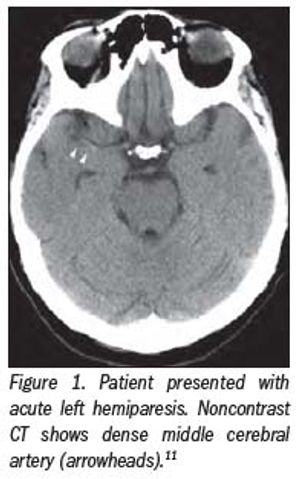

CT perfusion for stroke: Should you use it?

CT perfusion for stroke leaped from clinical discussion forums to the front pages in the last 13 months.